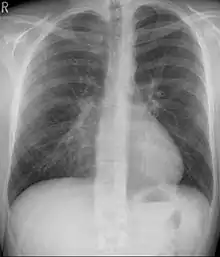

Chest x-rays are also useful in the diagnosis. The chest x-ray in pectus excavatum can show an opacity in the right lung area that can be mistaken for an infiltrate (such as that seen with pneumonia).[20] Some studies also suggest that the Haller index can be calculated based on chest x-ray as opposed to CT scanning in individuals who have no limitation in their function.[21]